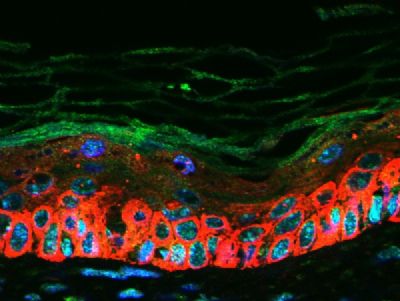

| 产品图片 |  Sample: BV2 Cell (Mouse) Lysate at 40 ug Primary: Anti- CXCL16 (bs-1441R) at 1/300 dilution Secondary: IRDye800CW Goat Anti-Rabbit IgG at 1/20000 dilution Predicted band size: 27 kD Observed band size: 27 kD  Tissue/cell: human lung carcinoma; 4% Paraformaldehyde-fixed and paraffin-embedded; Antigen retrieval: citrate buffer ( 0.01M, pH 6.0 ), Boiling bathing for 15min; Block endogenous peroxidase by 3% Hydrogen peroxide for 30min; Blocking buffer (normal goat serum,C-0005) at 37℃ for 20 min; Incubation: Anti-CXCL16 Polyclonal Antibody, Unconjugated(bs-1441R) 1:200, overnight at 4°C, followed by conjugation to the secondary antibody(SP-0023) and DAB(C-0010) staining  Images kindly provided by Dr. Denny Cottle from the publication, Fetal inhibition of inflammation improves disease phenotypes in Harlequin Ichthyosis.Formalin-fixed and paraffin embedded mouse skin probed with Rabbit Anti-CXCL16 Polyclonal Antibody (bs-1441R) at 1:50 for two hours at room temperature (green channel).  Paraformaldehyde-fixed, paraffin embedded (Rat colon); Antigen retrieval by boiling in sodium citrate buffer (pH6.0) for 15min; Block endogenous peroxidase by 3% hydrogen peroxide for 20 minutes; Blocking buffer (normal goat serum) at 37°C for 30min; Incubation: Anti-CXCL16 Antibody, conjugated (bs-1441R-AF488) at 1:100 overnight at 4°C; DAPI (5ug/ml, blue, C-0033) was used to stain the cell nuclei.  Blank control: A431. Primary Antibody (green line): Rabbit Anti-CXCL16 antibody (bs-1441R) Dilution: 3μg /10^6 cells; Isotype Control Antibody (orange line): Rabbit IgG . Secondary Antibody: Goat anti-rabbit IgG-AF647 Dilution: 3μg /test. Protocol The cells were incubated in 5%BSA to block non-specific protein-protein interactions for 30 min at at room temperature .Cells stained with Primary Antibody for 30 min at room temperature. The secondary antibody used for 40 min at room temperature. Acquisition of 20,000 events was performed. |